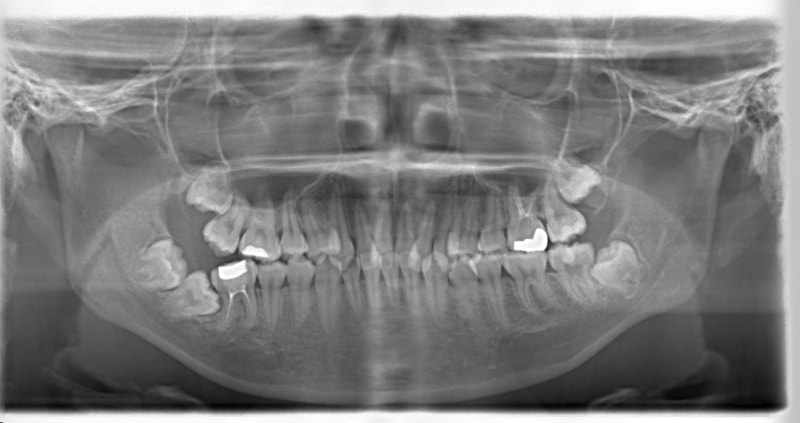

上顎前突+右下7番重度埋伏

(右下7番目の永久歯が下顎の中に埋まったまま、親知らずが上に乗っている)

治療法:フルパッシブブラケット:T21

解説:右下7番を抜歯し、右下8番を開窓牽引しました。近年、顎が退化しており、歯の大きさとの不調和がどんどん強くなりつつあります。2018年の矯正学会でも、本症例と同様の下顎7番8番の問題ケースが講演で紹介されておりました。こうなる前に、先手を打ちたいものです。小児の間に先行治療できるのがベストですので、お子様が6才になったら矯正専門医院に初診相談に行くようにしましょう。やる必要があるかどうかを聞きに行くのです。